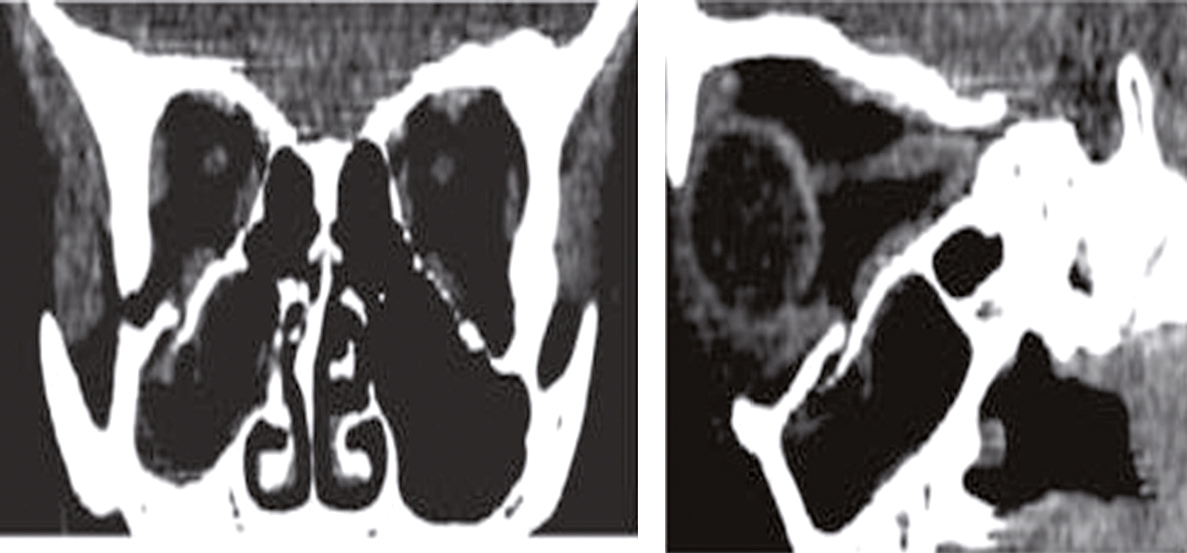

Fig. 13.6

Fracture du plancher de l’orbite.

Le scanner cérébral montre une fracture du plancher de l’orbite droite, avec incarcération du muscle droit inférieur.Une fracture du plancher de l'orbite est une rupture de l'os sous l'œil causée par un traumatisme facial, tel qu'un coup direct. Les symptômes incluent douleur, gonflement, ecchymoses, vision double, et mobilité réduite de l'œil. Parfois, l'œil peut sembler enfoncé ou déplacé. Le diagnostic est confirmé par des radiographies ou des tomodensitogrammes (CT scans), qui montrent l'étendue de la fracture et permettent d'évaluer les dommages aux structures environnantes. Le traitement dépend de la gravité de la fracture. Dans les cas moins graves, un traitement conservateur avec des analgésiques et des antibiotiques peut suffire. Les cas graves nécessitent souvent une intervention chirurgicale pour réparer l'os fracturé et repositionner les structures de l'œil. Il est crucial de surveiller les signes de complications, tels que des changements dans la vision, une douleur accrue ou des signes d'infection. Une prise en charge rapide et appropriée est essentielle pour minimiser les risques de complications à long terme et assurer une récupération optimale. En résumé, une fracture du plancher de l'orbite implique une rupture de l'os sous l'œil, diagnostiquée par imagerie et traitée en fonction de la gravité.